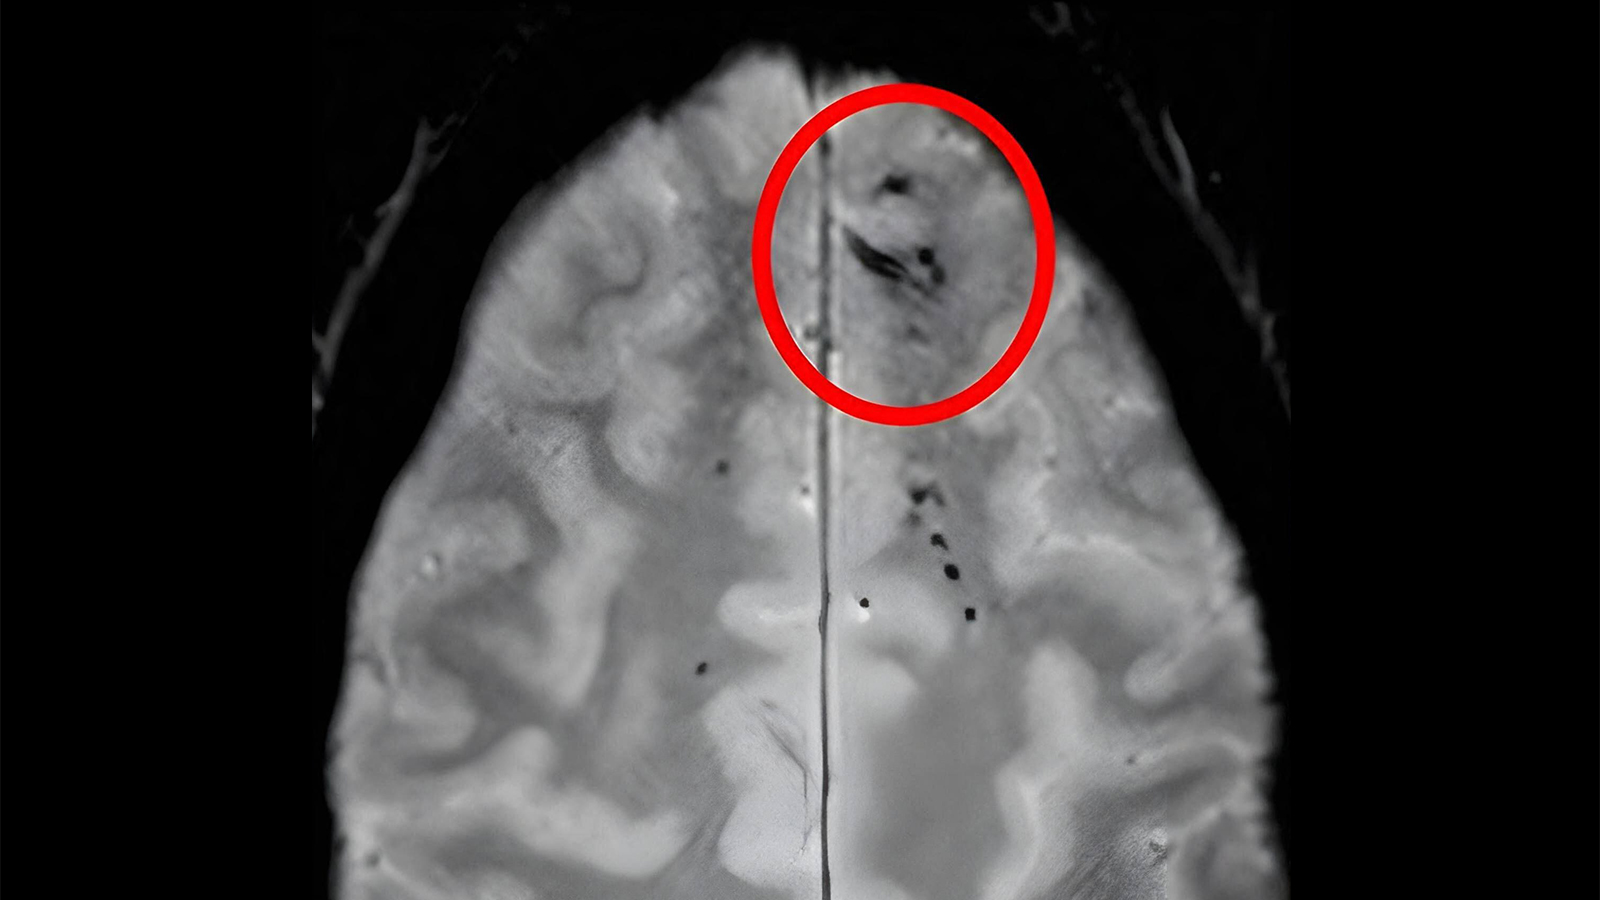

(MedPage Today) — The location and amount of brain microbleeds that a person has could be telling of their risk of dementia, according to an observational analysis.

Compared with controls with no cerebral microbleeds detected on MRI, there was…